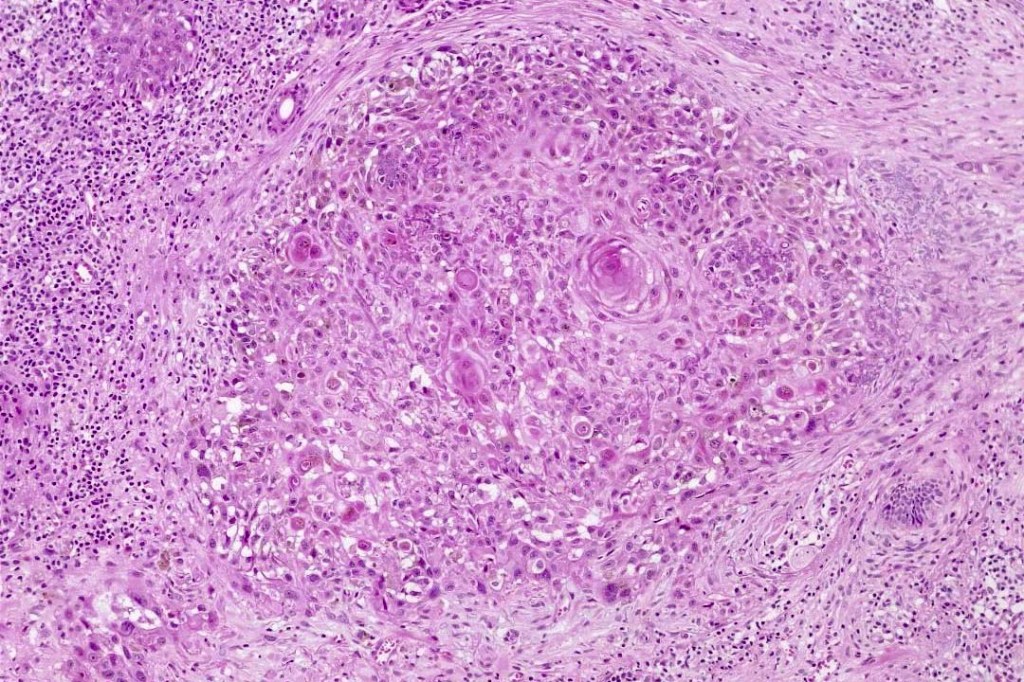

An exceedingly rare collision tumor composed of an admixture of squamous cell carcinoma/basal cell carcinoma/trichoblastoma respectively and melanoma. Although most appear to have behaved in a benign fashion, a malignant basomelanocytic tumor is illustrated below. More cases will be need to be stidies/published before the true biological behavior of this group of tumors can be satisfactorily elucidated. I think that complete excision should be the rule and a careful follow-up recomended.

Basomelanocytic tumor